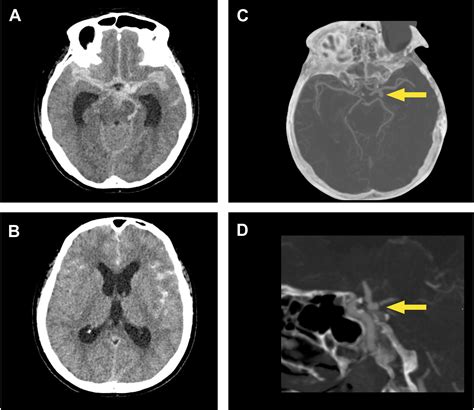

The Importance of CT Angiography (CTA)

While the initial Subarachnoid Hemorrhage CT is used to detect the presence of blood, it does not always reveal the source of the bleeding. Once a hemorrhage is confirmed, clinicians typically transition to a CT Angiography (CTA). This procedure uses a contrast dye injected into the bloodstream to create detailed, three-dimensional images of the brain's vascular structure. The goal of the CTA is to identify the underlying cause, such as an aneurysm, which may require surgical clipping or endovascular coiling.

The transition from a standard scan to an angiographic scan is seamless in most modern facilities. The vascular imaging allows neurosurgeons and interventional neuroradiologists to plan the necessary interventions immediately. Understanding the vascular map is essential for preventing re-bleeding, which carries a much higher mortality rate than the initial event.